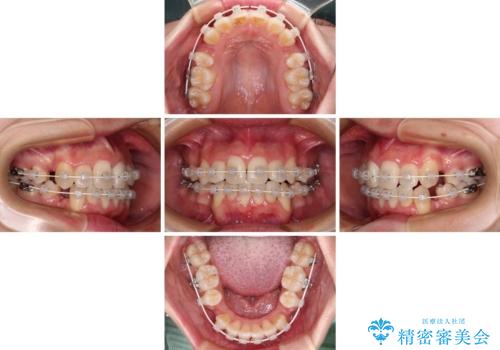

デコボコと出っ歯 抜歯矯正でスッキリとした口元に

- 上下前歯の八重歯やデコボコと、唇の閉じにくさを気にして来院された患者様です。

口元の突出感を改善するため、上下左右の第一小臼歯4本を抜歯し、ワイヤー装置にて矯正治療を行うこととしました。

デコボコの解消で歯が磨きやすくなり、抜歯矯正により口元の突出感が大幅に改善され、スッキリした口元になりました。